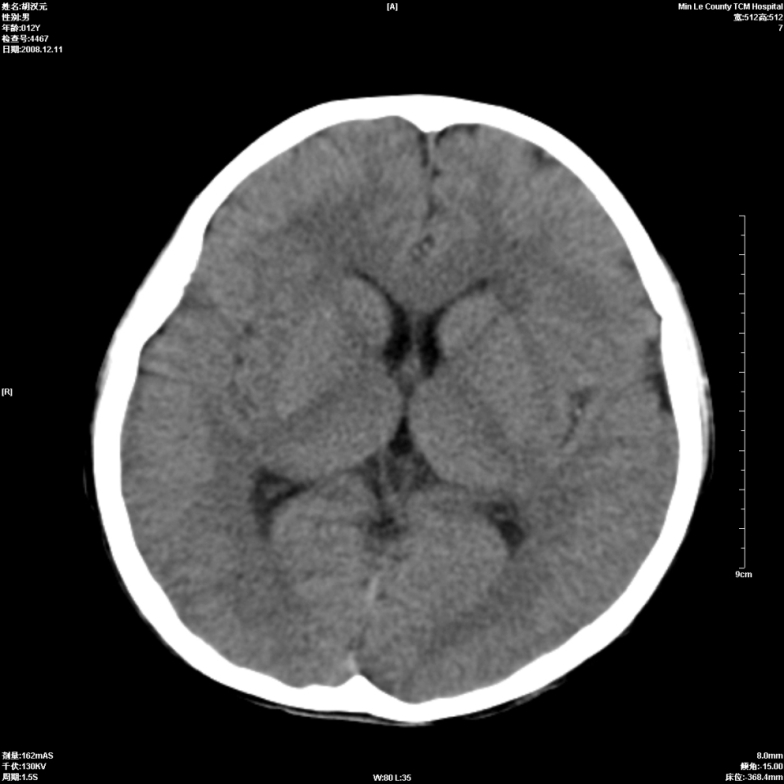

标题: PED1681:头疼发热约一周 [打印本页]

标题: PED1681:头疼发热约一周

颅脑未见确切异常。必要时进一步检查,如mri、脑脊液检查。

两侧顶部近灰质处白质密度降低,是否炎性改变

颅脑ct轴位平扫颅内未见明确异常;建议必要时复查或行进一步检查。

两侧顶部近灰质处白质密度降低,建议mri